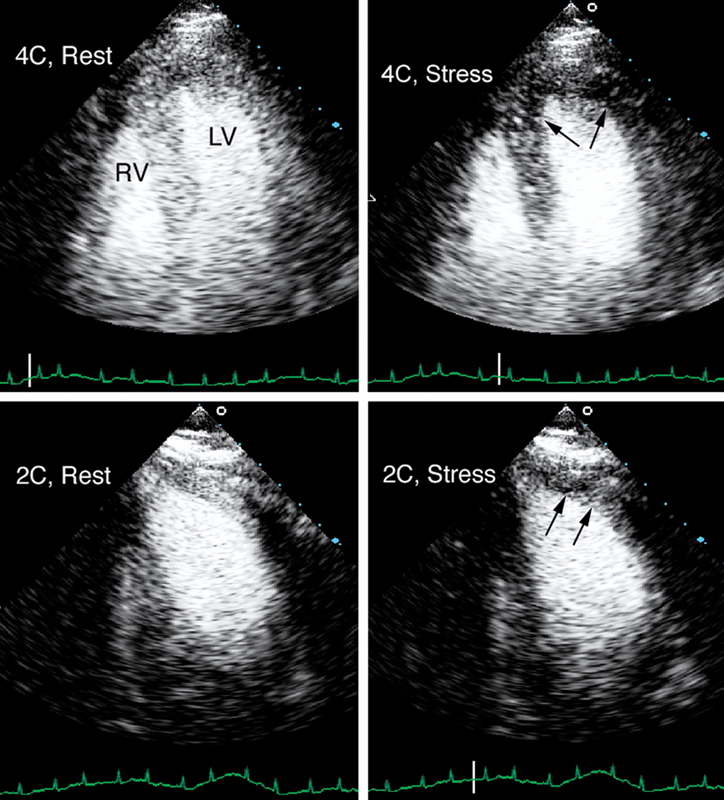

فحوصات تشخيصية لبعض امراض القلب والشرايين التاجية